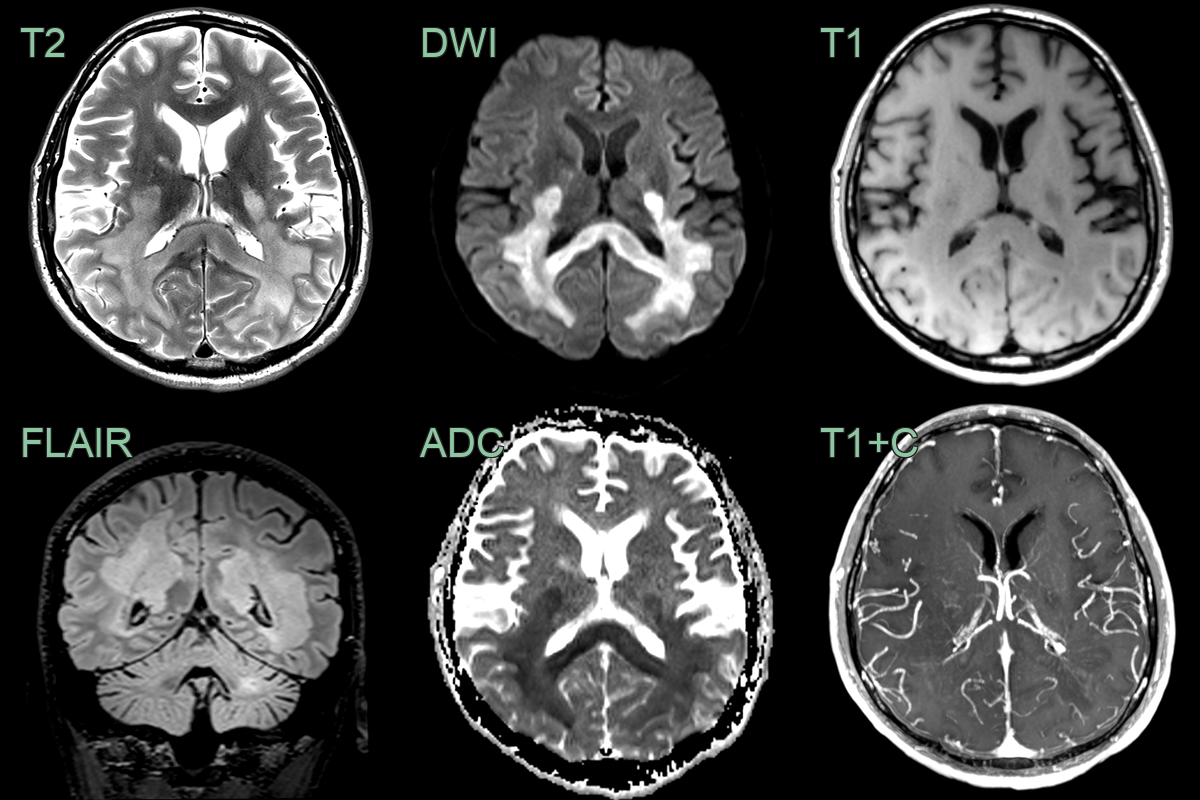

- A 30-year-old male with a known diagnosis of RRMS presented with a deterioration in motor function.

- MRI showed a large conflent diffusion restricting lesion within the posterior cerebral white matter and corpus callosum.

- The minimal contrast enhancement and only mildly elevated CBV made a lymphoma less likely.

- Biopsy confirmed tumefactive demyelination.